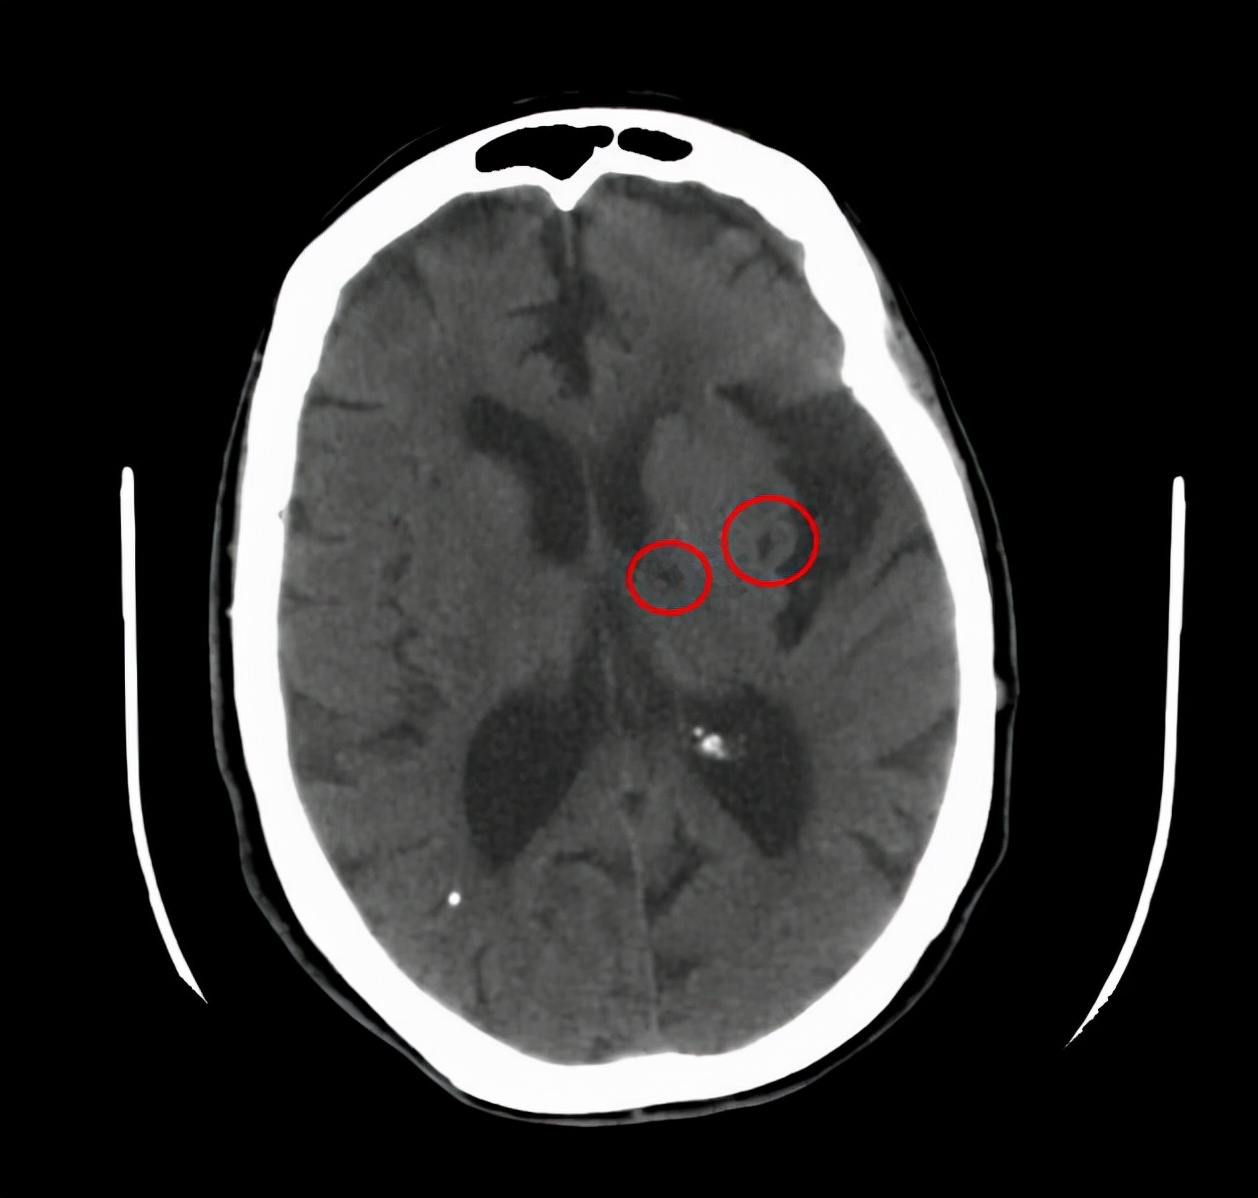

二、无症状的腔梗。

如果出现腔隙性脑梗死该怎么办呢?

当然,这个问题其实也应该分情况讨论。

如果有了具体症状,腔梗还是该治疗的,比如一侧肢体的运动感觉障碍,这个时候要小心,具体怎么治疗还是听医生的吩咐比较好。

但是如果没什么表现,仅仅是在体检或者在检查其他疾病的过程中发现有腔梗,这个时候该怎么办呢?

临床当中这种情况是很常见的,我们称为无症状的腔隙性脑梗死,对于这类患者,请您别害怕。

虽然我们称之为脑梗死,但他对我们的危害并不大,只需要改善生活方式,积极预防下一次腔梗就可以了。

都不用,千万别被骗。